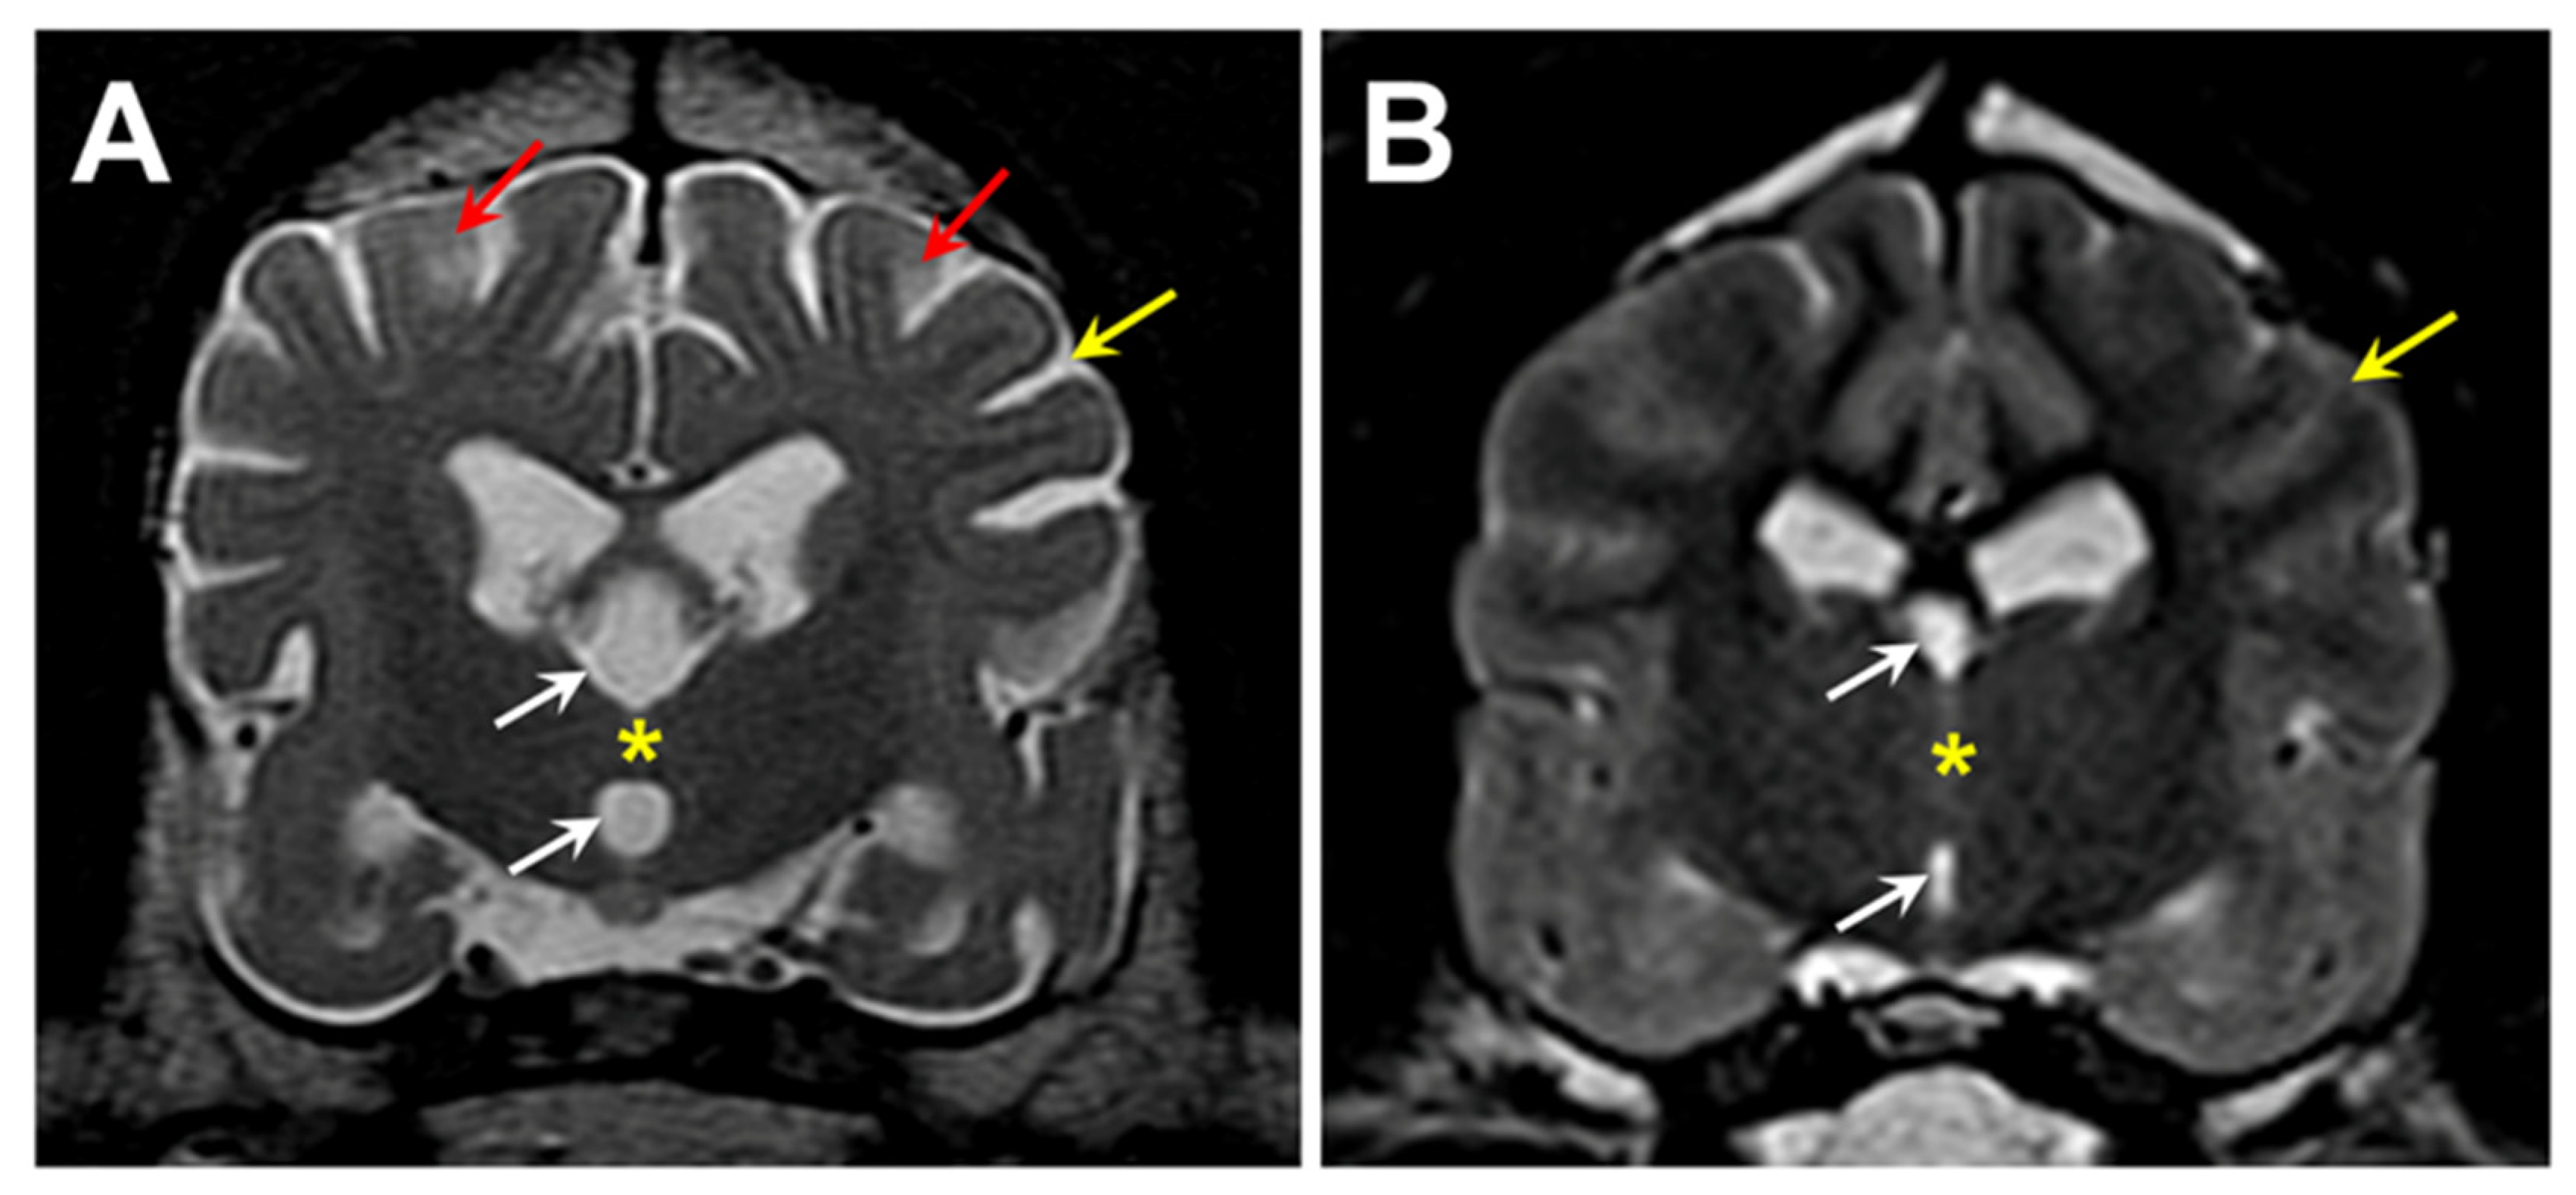

Figure 1. T2-weighted transverse MR images of the brain from the level of the interthalamic adhesion from the proband (A) and from an age- and weight-matched control diagnosed with idiopathic epilepsy (B). The proband exhibited cerebral parenchymal atrophy characterized by an abnormally small interthalamic adhesion (yellow asterisks), an enlarged third ventricle (white arrows), and widened subarachnoid spaces (yellow arrows). Areas of increased signal intensity within the cerebral cortex parenchyma white matter were also present (red arrows).

A 5-year, 1-month old neutered male Weimaraner (proband) was presented for neurological evaluation by a veterinary neurologist (MS) for an approximately 3-month history of pelvic limb ataxia, episodes of fecal incontinence, and lethargy. On neurologic examination, the proband was ambulatory with moderate paraparesis and proprioceptive pelvic limb ataxia characterized by a long-strided pelvic limb gait. A myelopathy was suspected. Standard MR images (1.5 Tesla instrument) of the thoracolumbar and cervical spine was performed and no significant spinal cord abnormalities were identified. Additional MR imaging of the brain was performed (T2-weighted sagittal, dorsal, and transverse images; T1-weighted post-gadolinium contrast sagittal, dorsal, and transverse images; FLAIR and T2-weighted gradient echo transverse images), which revealed pronounced cerebral parenchymal atrophy (Figure 1). Cerebrospinal fluid analysis was unremarkable. Based on these findings a neurodegenerative disease process was suspected. Approximately 1.5 years after the initial onset of clinical signs, humane euthanasia was elected due to the progression of neurologic dysfunction that included increased falling, worsening fecal incontinence, cognitive decline, incoordination, decreased interest in food, changes in posture, and episodes of trance-like behavior.